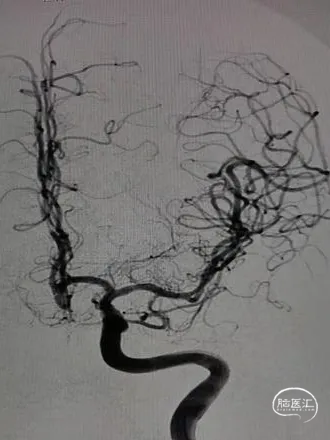

术前影像

栓塞过程

栓塞微导管精准塑形后,前推顺利到位,依次填塞三枚Jasper®SS弹簧圈。瘤颈处有壶腹,为增加弹簧圈稳定性,降低动脉瘤复发率,释放支架,复查造影,动脉瘤填塞致密,载瘤动脉通畅良好。

术后即刻影像